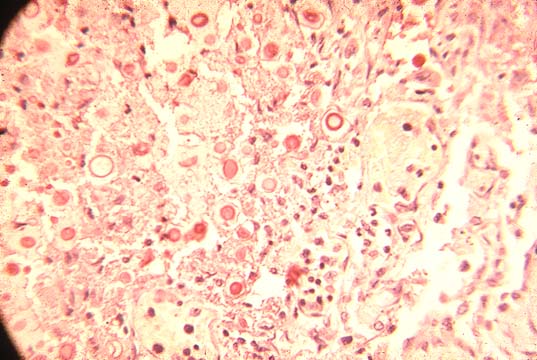

Same granuloma

Fig.139-Same granuloma

with acid-fast stain. The acid-fast organisms, red, are agglomerated inside histiocytes.